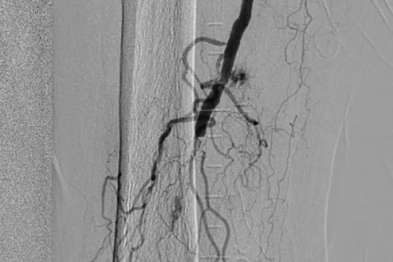

【协作组解病忧】高龄不设限,二附院救治 90 岁下肢动脉闭塞患者